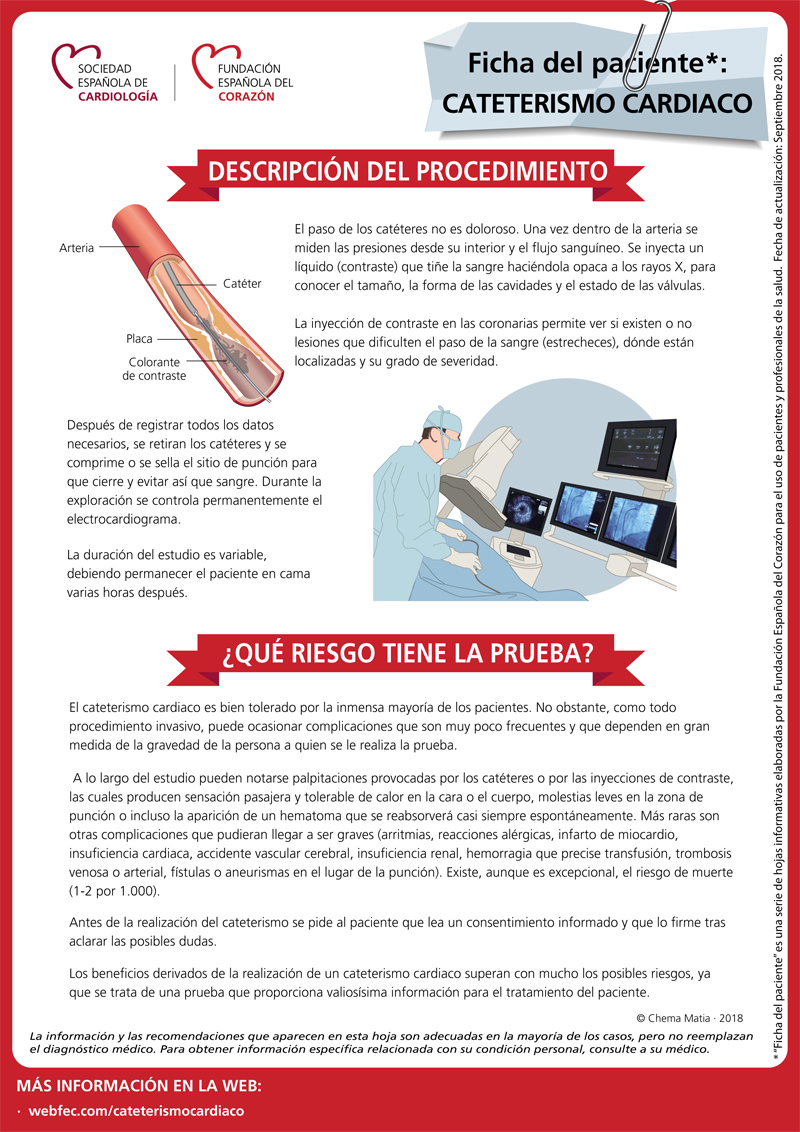

¿Cómo se realiza el cateterismo diagnóstico? ¿En qué casos está indicado? El Dr. Manuel Pan, jefe del Servicio de Cardiología de Hospital Universitario Reina Sofía, lo explica en este vídeo: fundaciondelcorazon.com/corazon-facil/…